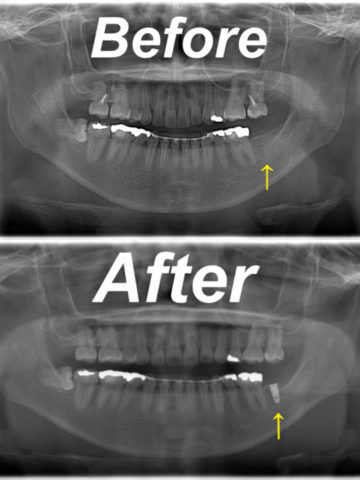

インプラント

インプラント + 付着歯肉移植術

年代/性別

50代/女性

症状

奥歯を入れたい

治療方法

FGG(遊離歯肉移植)

費用

インプラント 440000円

FGG(遊離歯肉移植)110000円

備考

オペを2回要する